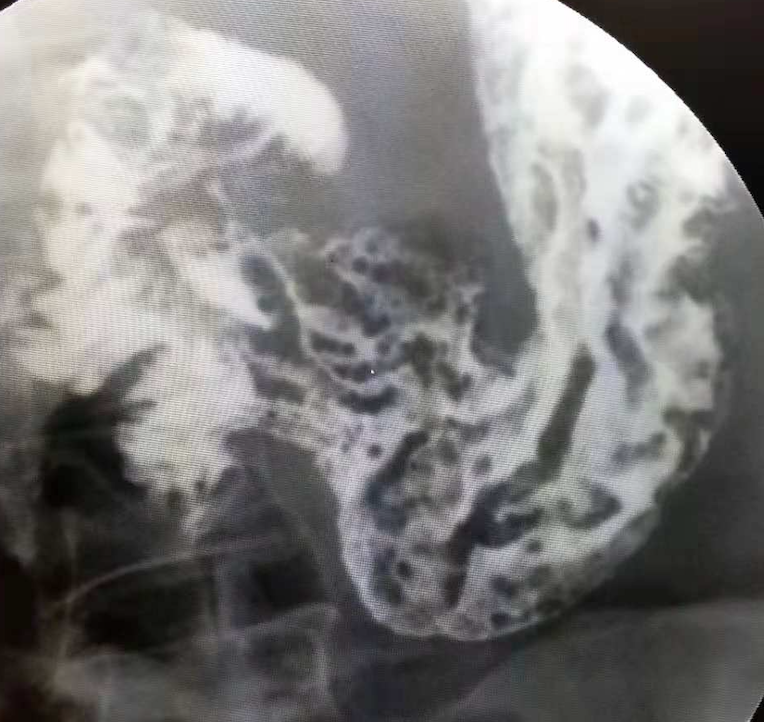

胃镜检查发现胃内多发丘疹样息肉,大小不等,1mm~30mm,表面光滑,息肉间黏膜凹凸不平,多发于胃窦、幽门,胃底胃体也可发生。息肉的性质为错构瘤性息肉。(如图)

胃肠数字化造影检查发现胃粘膜增粗,并见多发小的充盈缺损(如图)。